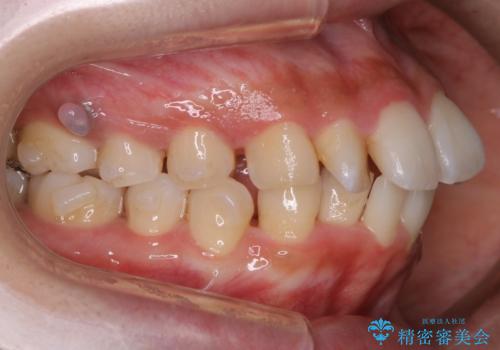

- 歯のガタつきと口元の突出感を主訴に来院されました。

装置の希望がインビザラインだったため、非抜歯でインビザラインの特徴を最大限に生かして行う矯正治療を選択しました。

一般的に口元を下げるための治療というと抜歯矯正を思い浮かべる方が多いかと思います。そもそもガタつきを治したり歯を引っ込めるためのスペースの作り方には大きく分けて4種類の方法があります。

①抜歯 ②歯列の幅の拡大 ③IPR(歯の幅を削って小さくする) ④歯の後方移動 です。

インビザラインの登場により抜歯以外の3種類の方法を効率よく活用することができるようになりました。

そのため、非抜歯でも口元の環境が改善するケースがあります。